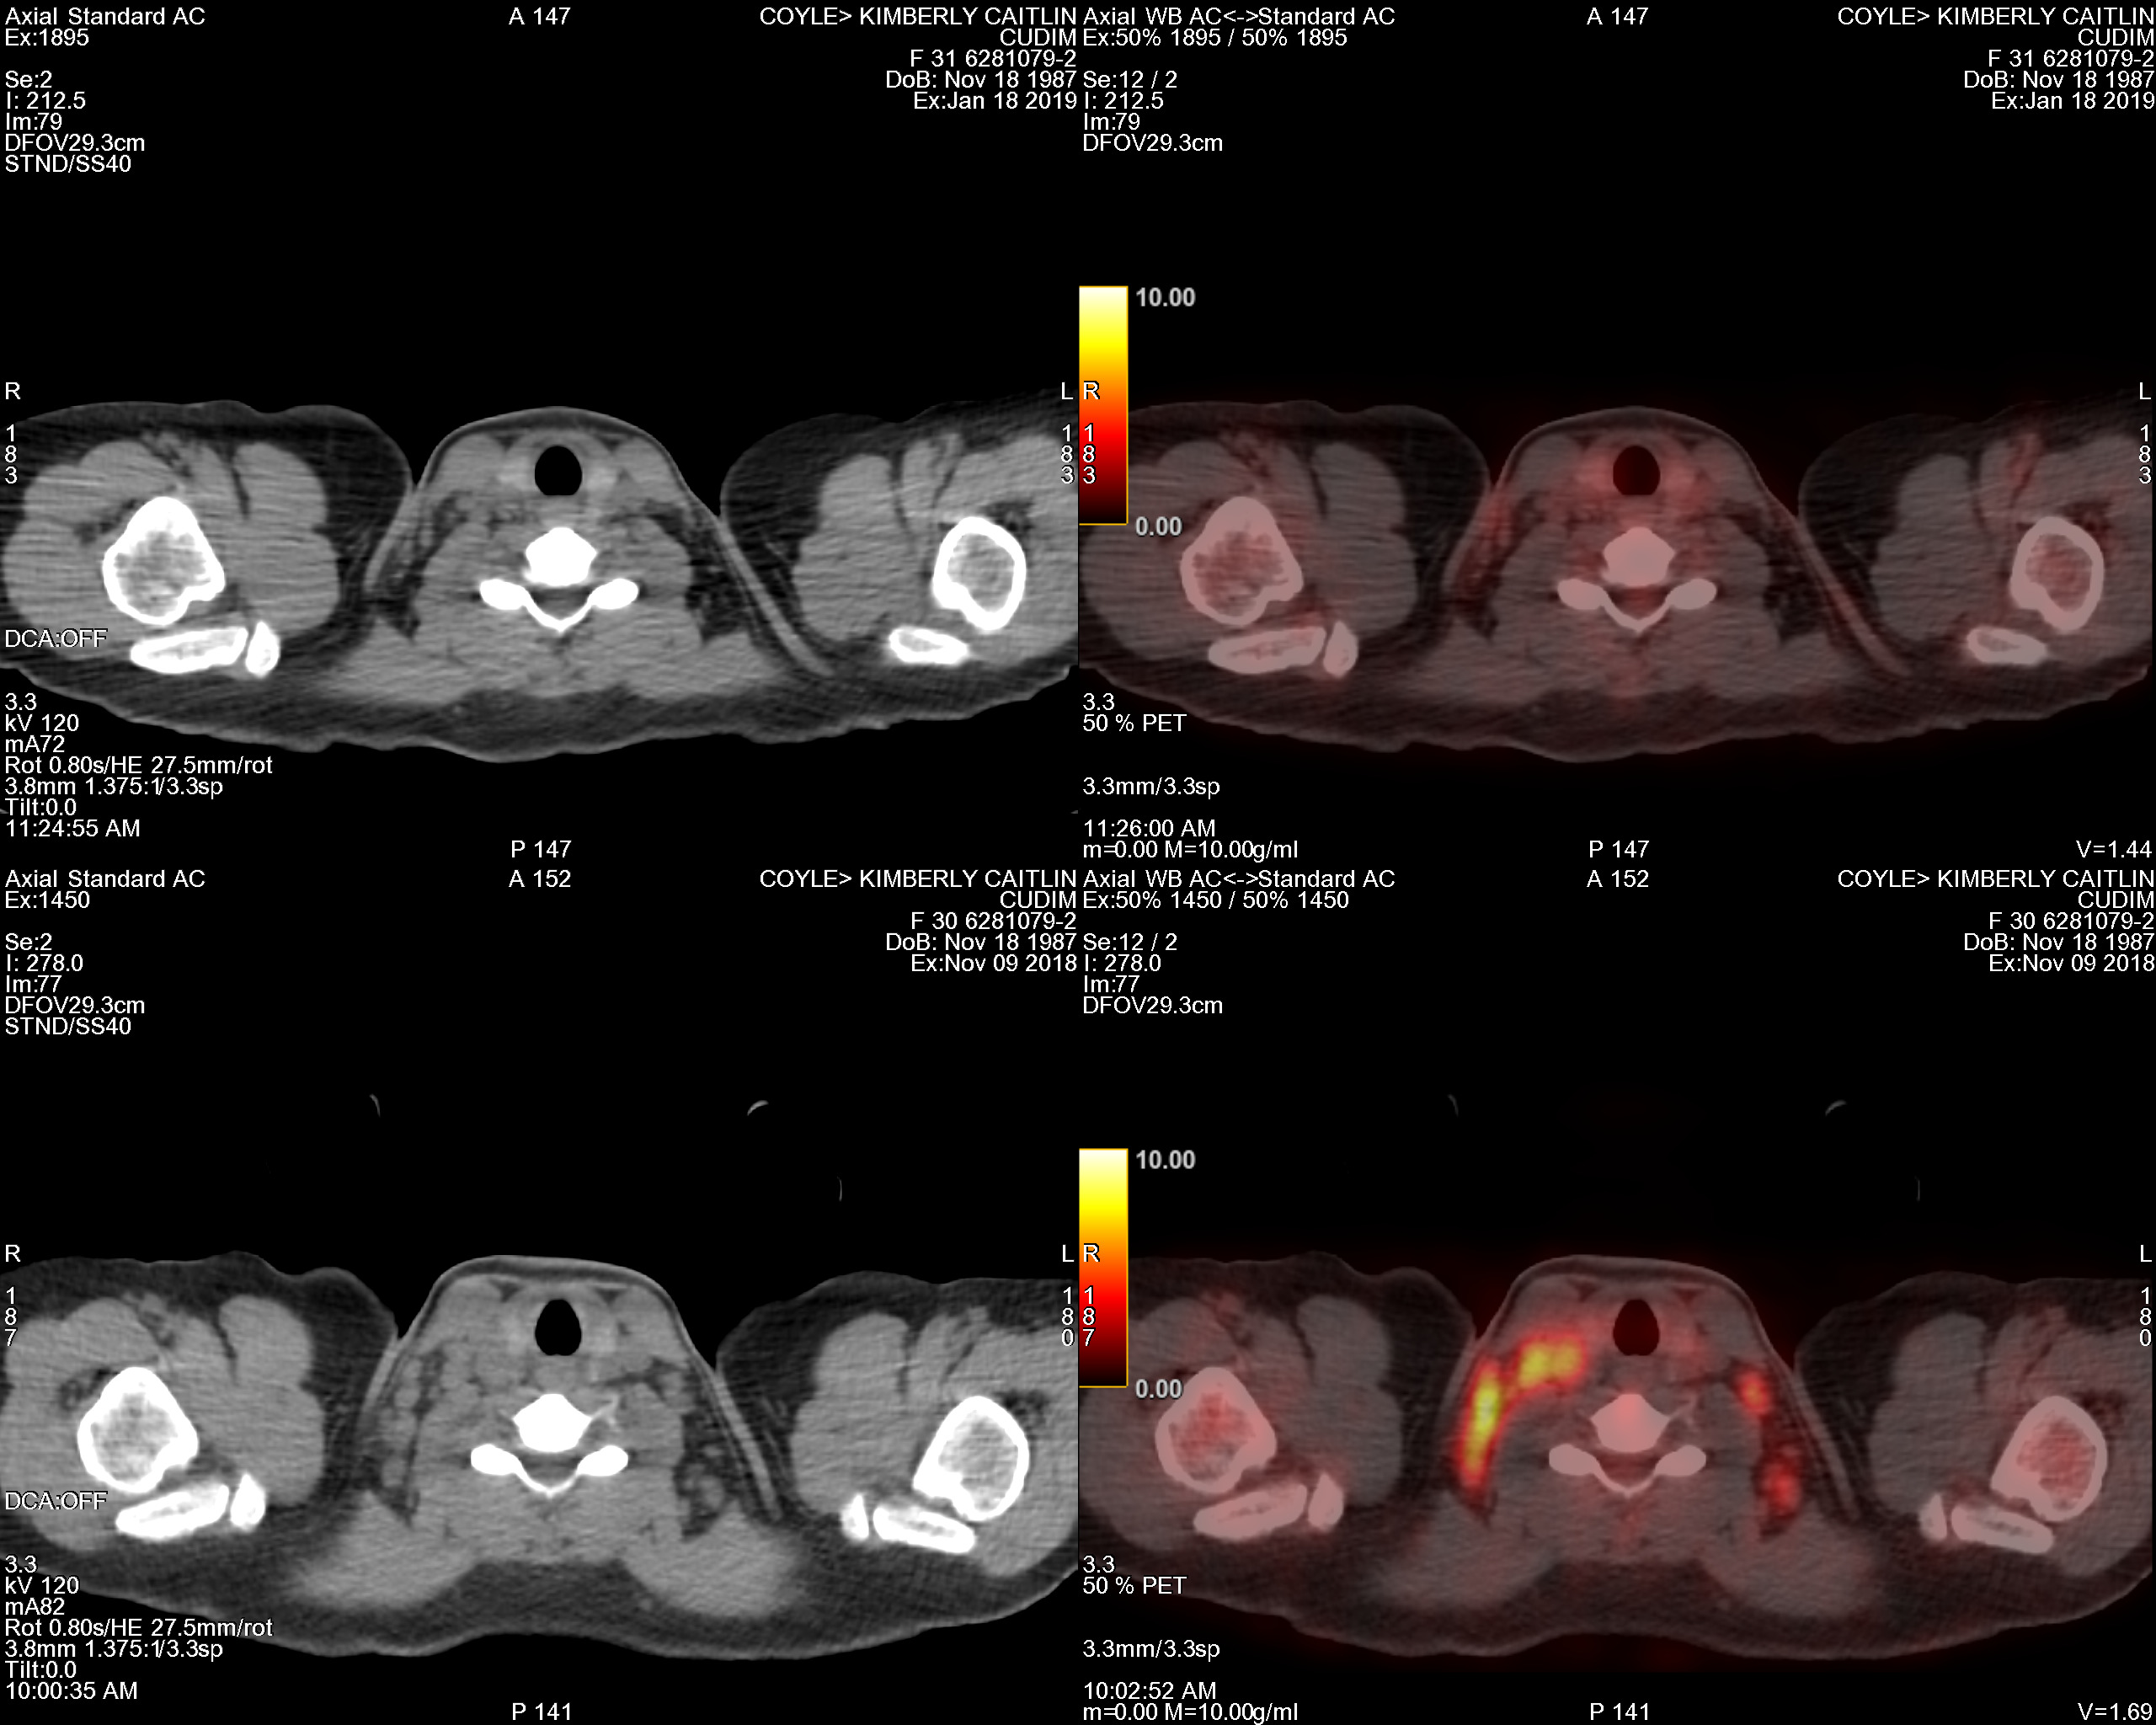

PET Scan Number Two

The Results Are In…Chemo Works